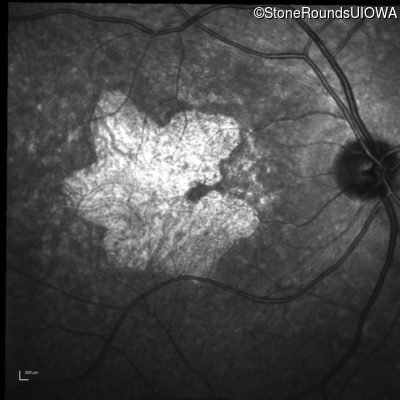

Infrared Fundus Photograph - Left - 20/20 -2

Exemplar